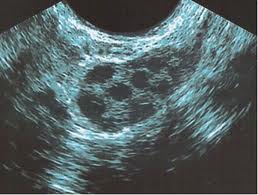

Buenos días. Acabo de someterme a una segunda fiv y me encuentro con la recuperación de 4 ovocitos, el resto folículo vacío.Me gustaría saber a qué puede ser debido y si podría volver a sucederme en un nuevo intento.

Los valores que presentas de reserva ovárica son normales, probablemente la causa de que no en todos los folículos que se veían por ecografía hubiese ovocitos sea la edad. Creo que si tuviste finalmente buenos embriones para transferir se podría intentar de nuevo otro ciclo si no te quedas embarazada en este.